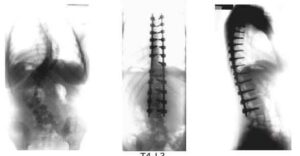

scoliosis

Migliorare il rapporto di fiducia fra medico e paziente e raccogliere dati reali che possano facilitare l’uso del corsetto. Questo l’obiettivo dello studio ”In difesa degli adolescenti: usano realmente il corsetto per le ore prescritte, se si offre un aiuto adeguato. Risultati di una coorte prospettica nell’uso clinico quotidiano del Thermobrace”, sviluppato un anno fa dai ricercatori di Isico (Istituto Scientifico Italiano Colonna Vertebrale) e pubblicato sulla rivista Scoliosis da BioMed Central. La pubblicazione ha raccolto un importante consenso sui principali network anglosassoni del settore.